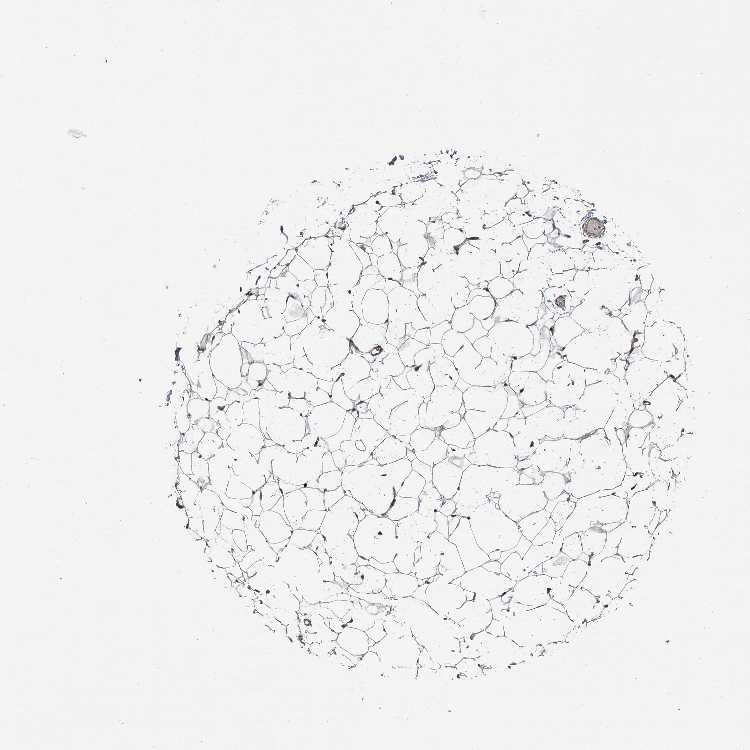

ADIPOSE TISSUE - Antibody stainingi

Antibody staining in the annotated cell types in the current human tissue is reported as not detected, low, medium, or high, based on conventional immunohistochemistry profiling in selected tissues. This score is based on the combination of the staining intensity and fraction of stained cells.

Each image is clickable and will lead to virtual microscopy that enables deeper exploration of all samples and also displays staining intensity scores, fraction scores and subcellular localization as well as patient and tissue information for each sample.

Antibody HPA038163Antibody HPA038164

Adipocytes Not detectedMedium